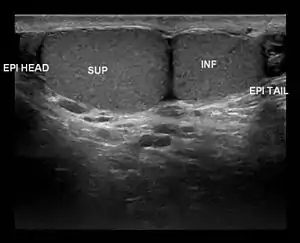

| Ultrasound scan showing a side view of Type A3 polyorchidism, with annotations showing the superior and inferior testes and the head and tail of the epididymis |

- Type A3: The supernumerary testicle shares the epididymis and the vas deferens of the other testicles.